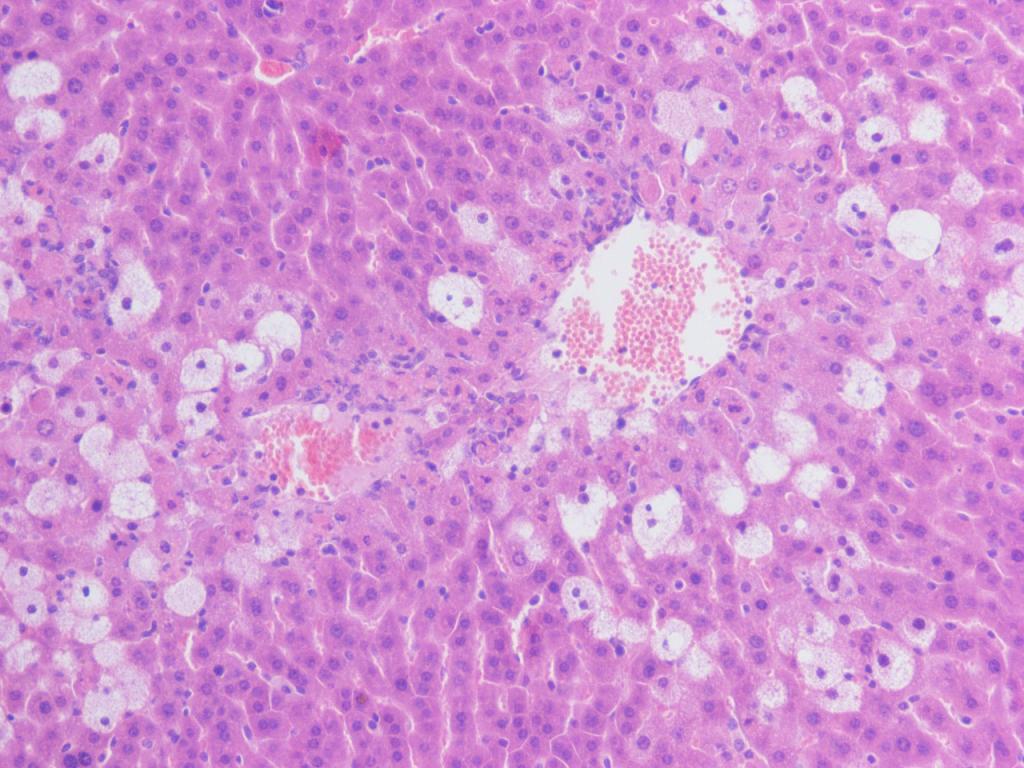

请问高人,肝脏损伤是先发生气球样肿胀,还是先紊乱? 我的这两张照片,哪个的损伤更严重? 第二张照片,气球样肿胀细胞周围有的细胞看上去是正常的,感觉像细胞受到损伤了但是在自行修复中。这个要怎么解释? 跪求高人帮我分析这两张照片!谢谢! 金币不够会追加! 2号 200-2.JPG A2 200-1.jpg [ Last edited by 暖麦 on 2013-2-5 at 17:01 ] |